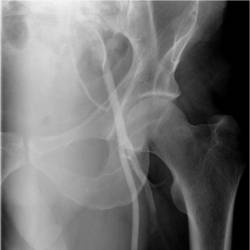

Physician Assistant Lower Limb and Thorax Written Examination - Radiology Pool

Gallery of Unlabled Radiographs from Lecture (Dr. French) - 2020

Click a thumbnail to enter the gallery display. Click the file name link at the bottom left of the gallery display to view the image at high resolution.